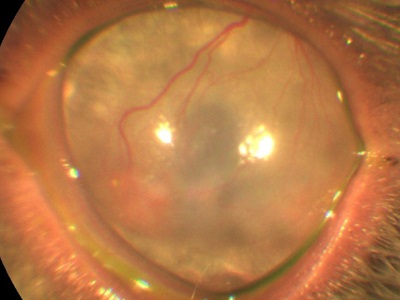

De exemplu, atunci când bariera este lovit stratul lichid intern al corneei - endoteliului. Unele rase de câini au o predispoziție genetică la o scădere a numărului de celule endoteliale, care este motivul pentru care se umfla corneei si devine alb. De asemenea, în cazul în care numărul acestor celule este prin natura prea puține animale, dar cu varsta ele devin chiar mai mici.

În acest context, se poate dezvolta edem excesiv de puternic, separarea corneei, formarea de bule specifice (Bull).

Sau fara celule endoteliale daunatoare

Tratamentul tuturor acestor patologii extrem de variably și include tratamentul medicamentos și chirurgical (plastic cornee, tarzorrafiya impact termic) depinde de starea ochiului.

creșterea presiunii intraoculare (glaucom) va acționa, de asemenea, asupra celulelor endoteliale prin deteriorarea acestora.